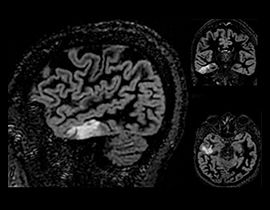

Diese Komplettlösung ermöglicht die Darstellung von Gehirn, Wirbelsäule, Gefäßsystem und peripherem Nervensystem mit außergewöhnlichem Gewebekontrast. Mit ihren bewegungsunempfindlichen Techniken ermöglicht sie die automatische Ausrichtung mit nur einem Klick und stellt eine vollständige Neurologie-Lösung vom Scan bis hin zur Nachbearbeitung bereit.

NeuroWorks beinhaltet auch Cube, unsere Suite für volumetrische 3D-Bildgebung, die für jedes System Standard ist. Mit dieser Anwendung können Sie die Hirn- und Rückenmarkflüssigkeit und entweder die weiße oder die graue Substanz unterdrücken, um die Sichtbarkeit von Läsionen zu erhöhen.

NeuroQuant segmentiert und misst automatisch die Volumen von Hirnstrukturen und vergleicht diese Volumen mit Normwerten. Anhand solcher Informationen unterstützt es die Diagnosestellung und die Beobachtung des Krankheitsverlaufs. NeuroQuant stellte Bericht zu einer Vielzahl klinischer Aspekte bereit, darunter zu altersbedingter Atrophie, Hippocampus-Volumenasymmetrie, Atrophie mehrerer Strukturen, Triage der Hirnatrophie, Gehirnentwicklung und allgemeiner Morphometrie.